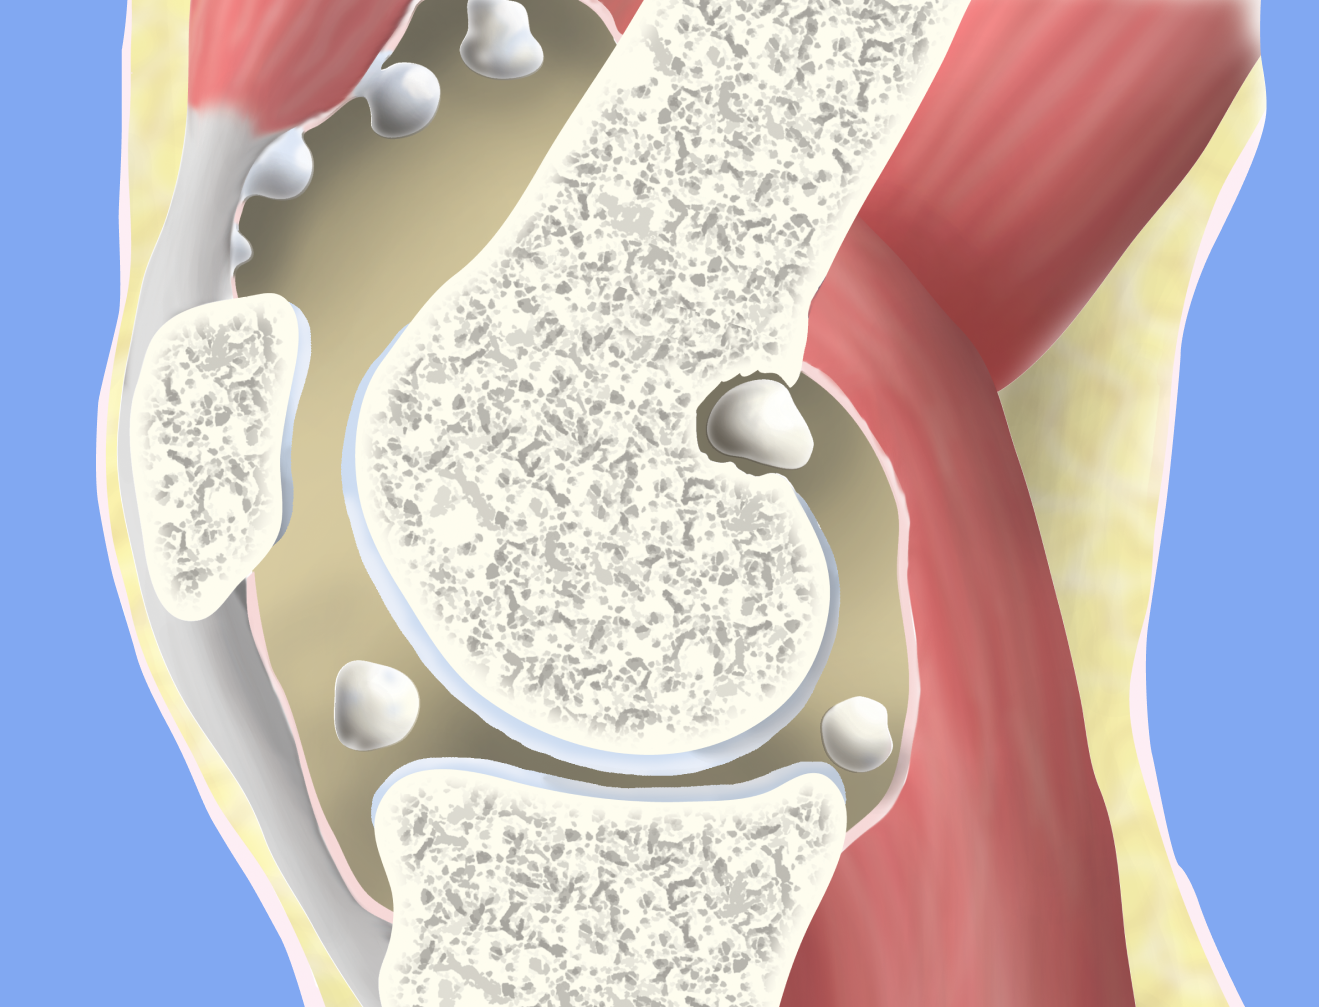

Хондроматоз – это патологическое изменение сустава, причиной которого становится перерождение синовиальной оболочки в хрящ. Это заболевание довольно редкое, может поражать любой сустав, но чаще всего страдает именно коленный сустав. Заболевание характерно для спортсменов и людей, подвергающихся регулярным тяжелым физическим нагрузкам, четкая причина возникновения неизвестна. Симптомы- боль, хруст и заклинивание сустава.